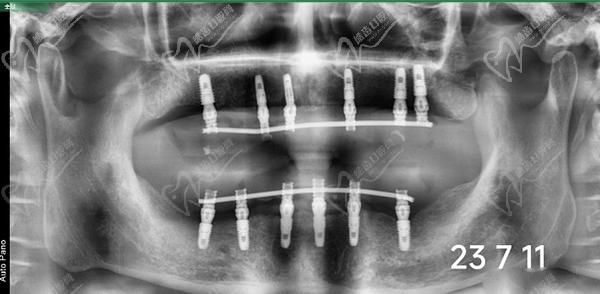

牙友1、前天結(jié)束的全口種植牙,拔牙加同期種12顆瑞士士卓曼,即刻負(fù)重!全口牙周炎伴隨多顆牙松動且骨量不足等問題,普通的種植手術(shù)無法滿足生活需求,想要做即拔即種即刻戴上臨時(shí)牙,因?yàn)槌R?guī)的植骨手術(shù)需要等待很長時(shí)間。經(jīng)過正規(guī)醫(yī)院骨質(zhì)評估分析,上頜AO4+兩邊穿翼手術(shù),患者手術(shù)結(jié)束當(dāng)天就可以正常用牙,本人表示非常高興和滿意!感謝醫(yī)院團(tuán)隊(duì)協(xié)作!